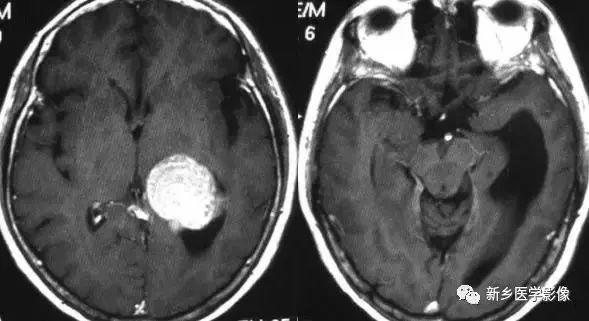

4.一侧室间孔阻塞

脑脊液主要产生于脑室的脉络膜丛。 当一侧室间孔阻塞时,同侧侧脑室脉络膜丛产生的脑脊液不能进入三脑室,脑脊液在侧脑室内聚积,CT和MR检查表现为一侧侧脑室扩大,扩大明显时可有中线结构向对侧移位,主要原因有室间孔附近的肿瘤、囊肿、囊虫及炎性粘连。 确定一侧侧脑室扩大为室间孔阻塞所致的要点包括:一侧侧脑室扩张明显,有张力.透明隔向对侧移位;扩一大的侧脑室周围没有能够导致该侧侧脑室扩大的其他可以解释的原因。